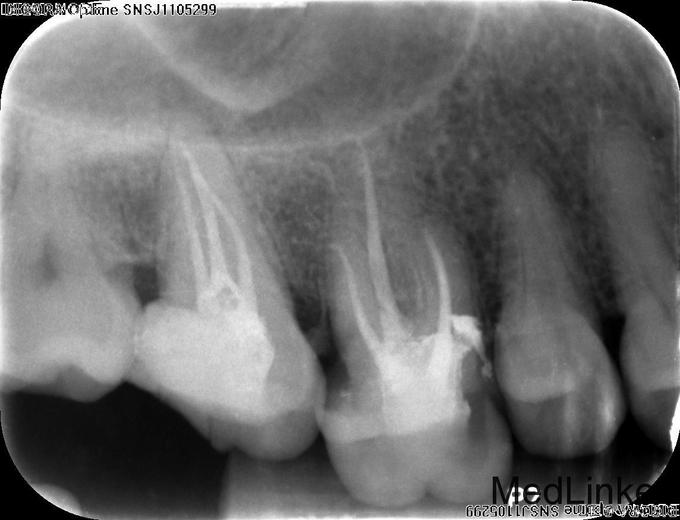

主诉:右上后牙反复食物嵌塞数年,疼痛3月 现病史:患者自述右上后牙进食时反复发生食物嵌塞,近三月嵌塞现象明显,并伴有疼痛,进食食物嵌塞时疼痛明显,偶尔伴有剧烈疼痛,于我院就诊,要求治疗。 既往史:否认牙科治疗时,否认全身系统疾病史及药物过敏史

检查:#17和#18间,#17和#16间,#16和#15间食物嵌塞,探及龋损,于#17远中和#16近中尤为明显,深探时引起患者不适,但无剧烈疼痛,换牙无松动,患牙冷诊发生疼痛,并持续数十秒,#17远中和#16远中谈及深牙周袋,探诊出血。 对合牙尖高耸。 x-ray示#17远中,#16近中深龋损,近牙髓。

诊断:#17、#16慢性牙髓炎 治疗: 调磨对合尖锐牙尖 #17、#16碧兰麻下开髓,封三甲+OC球,ZOE暂封; 2周后复诊去暂封,清理髓腔及根管,双氧水和生理盐水交替冲洗清空根管,分别测WL,手动+镍钛锉预备各根管,拍片试尖达工作长度,根管内导入糊剂,侧压充填中下段,热牙胶充填上段,X线示恰填,GIC暂封。转诊修复科行冠修复。并行系统牙周治疗,拔除智齿。